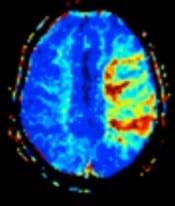

Perfusion Weighted Imaging

Perfusion MRI is a key tool in stroke assessment, providing valuable information about blood flow to the brain tissue. During a stroke, blood flow is disrupted, leading to ischemia (inadequate blood supply) in affected areas. Perfusion imaging in the case of acute stroke measures blood flow, volume, and transit time, helping clinicians to find regions of reduced perfusion, which may indicate areas at risk of irreversible damage, or penumbra (potentially salvageable tissue surrounding the core infarct). This information guides treatment decisions, such as the administration of thrombolytic therapy or mechanical thrombectomy, aiming to restore blood flow and minimise brain injury. Perfusion MRI also aids in predicting patient outcomes and assessing treatment response, helping personalised stroke management strategies for improved patient care and recovery.